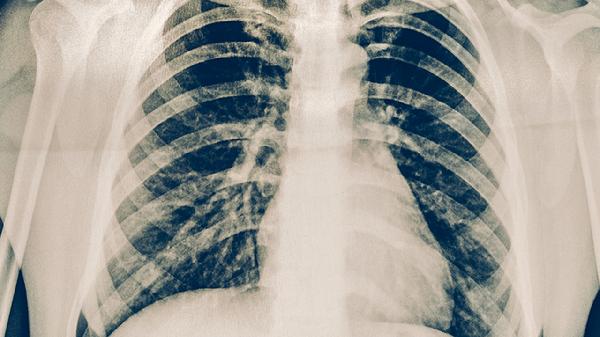

肺结核可通过抗结核药物治疗、手术治疗、营养支持、隔离防护、心理疏导等方式治疗。肺结核通常由结核分枝杆菌感染引起,表现为咳嗽、咯血、低热、盗汗、消瘦等症状。

肺结核患者需遵医嘱使用异烟肼片、利福平胶囊、吡嗪酰胺片、乙胺丁醇片、链霉素注射液等药物联合治疗。抗结核药物需规律服用6-9个月,不可自行停药。治疗期间可能出现肝功能损害、视神经炎等不良反应,需定期复查。

肺结核患者治疗期间需保证充足休息,避免过度劳累。每日开窗通风2-3次,每次30分钟以上。注意监测体温变化,记录痰液性状。严格遵医嘱用药,定期复查胸部X线片和痰结核菌检查。出现药物不良反应或症状加重时及时就医。治愈后仍需保持良好生活习惯,增强免疫力预防复发。